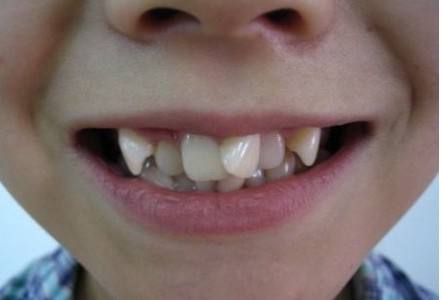

毕竟牙齿长成下面这样,再加上小伙伴三言两语的小绰号,日积月累宝宝们自然是难以开怀大笑了。

(需要矫正的情况,欢迎对号入座)